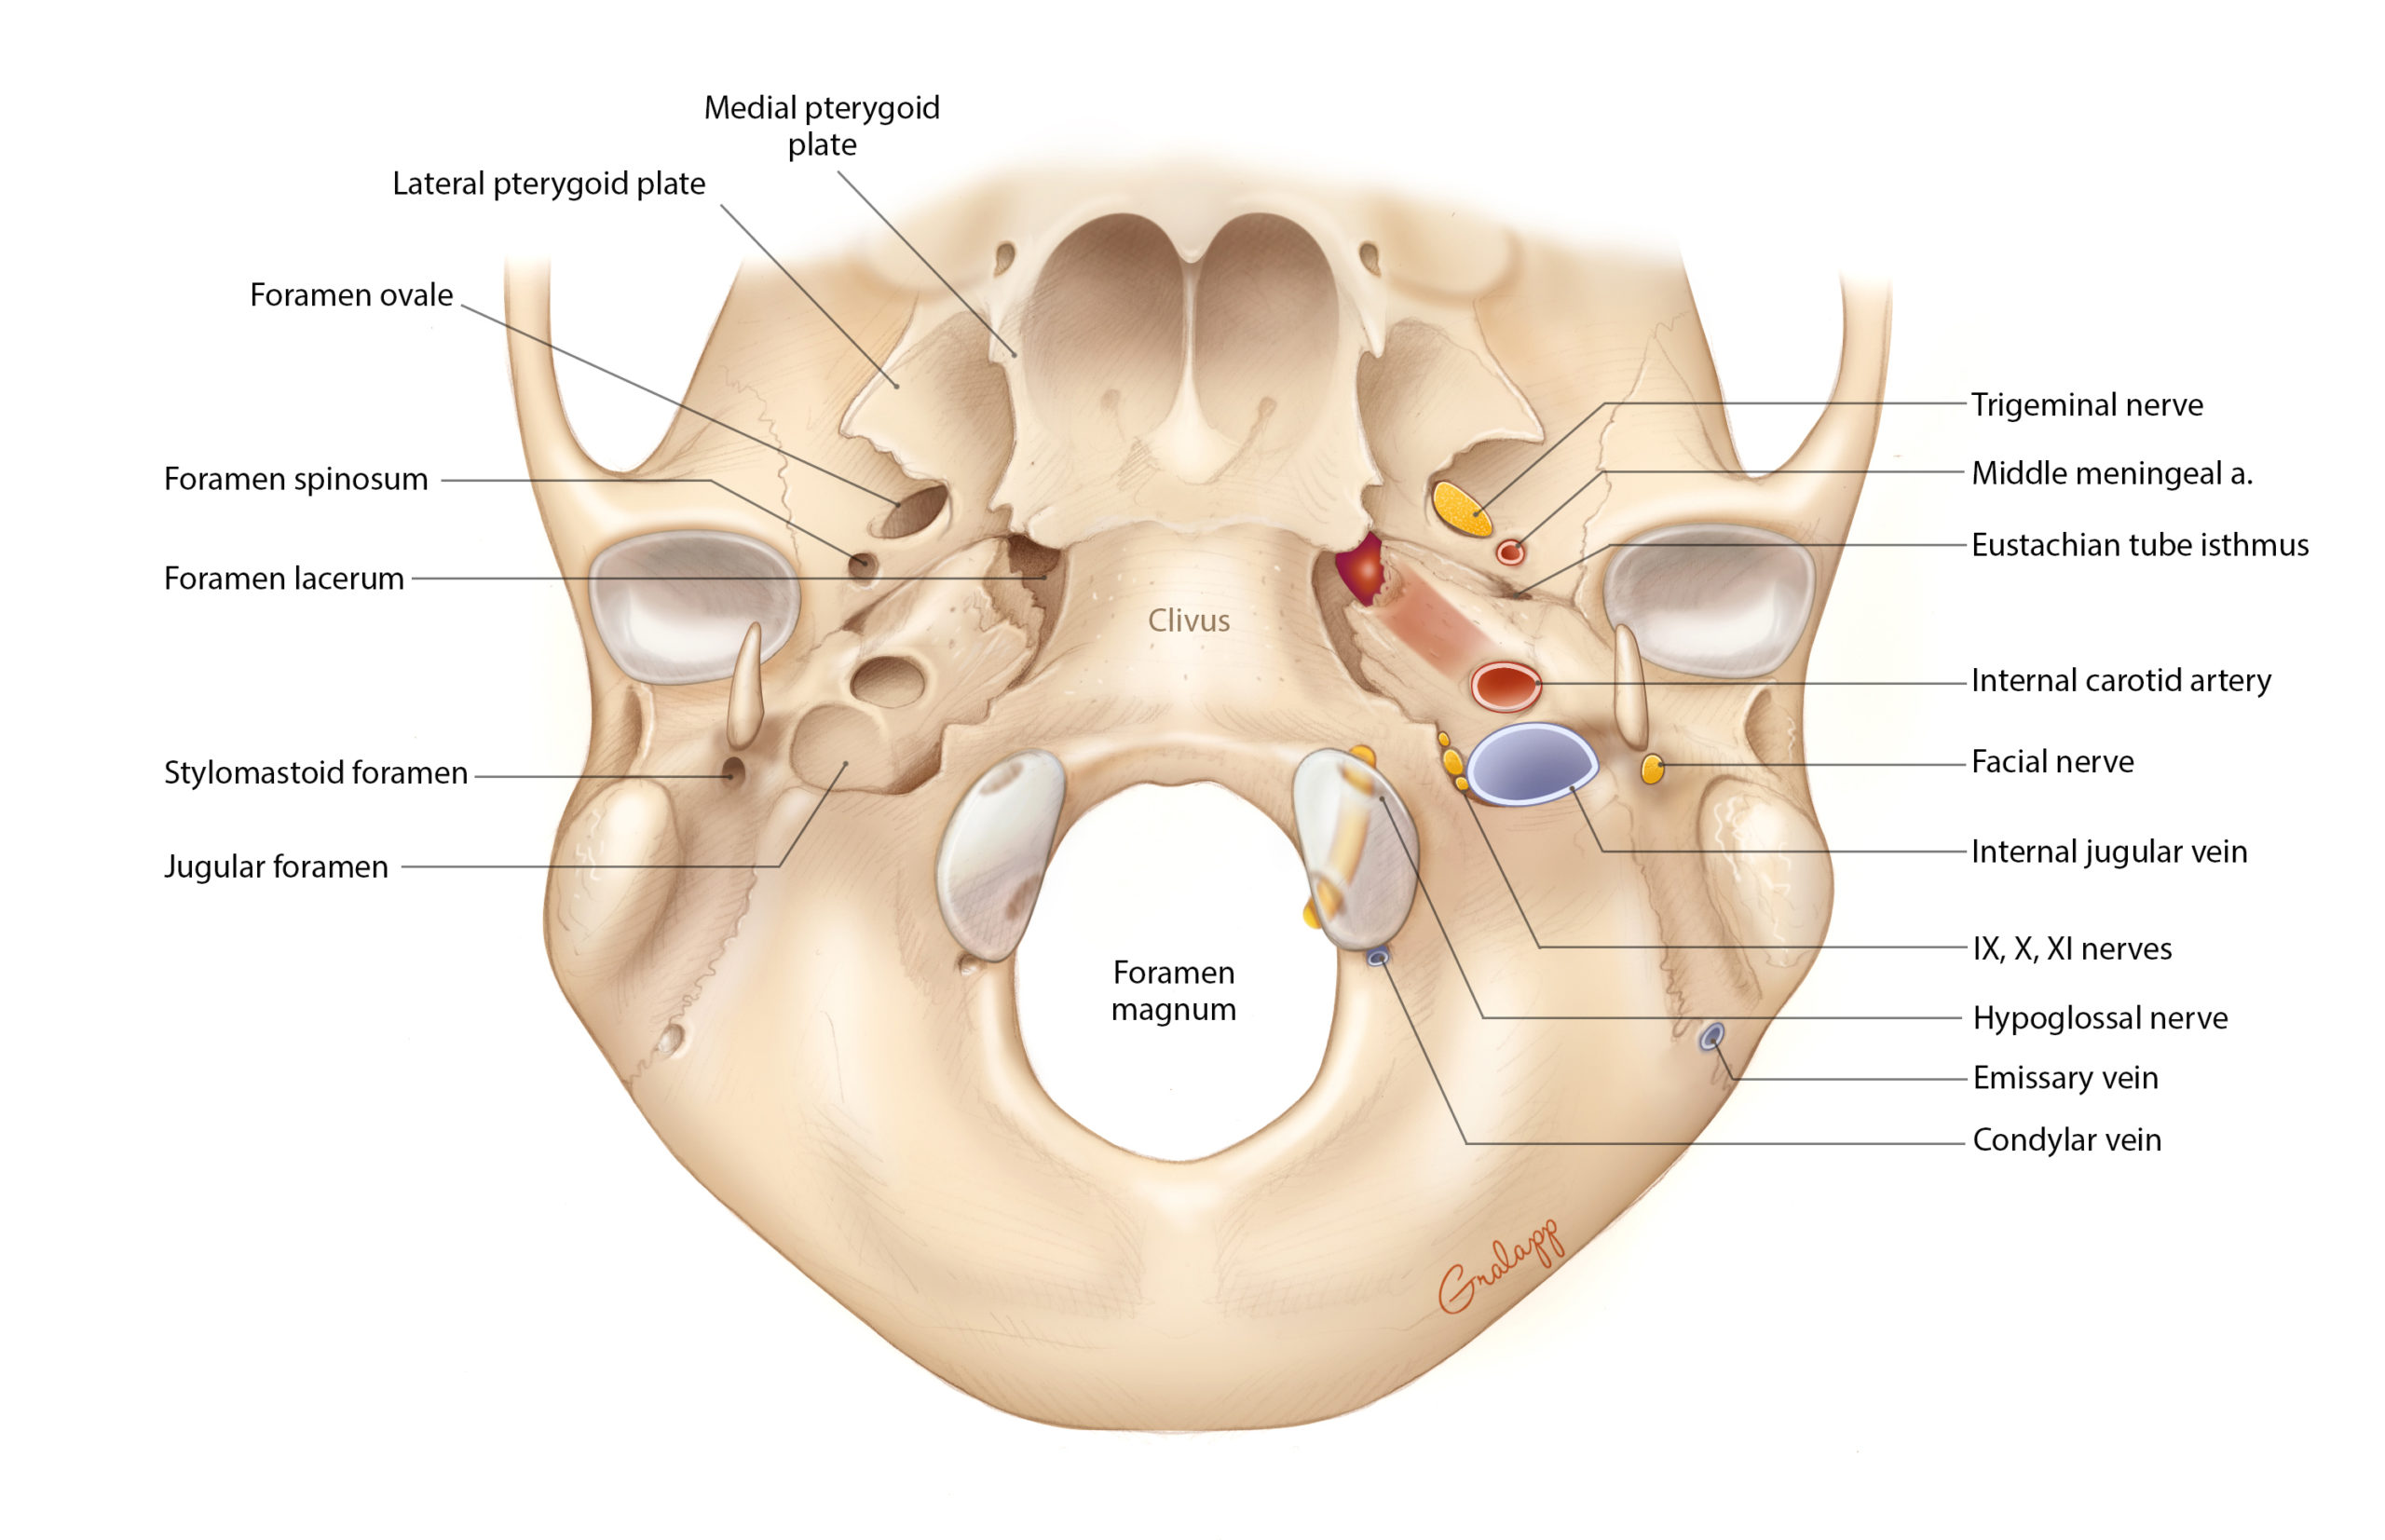

КТ анатомия сосцевидного отростка: особенности и показания